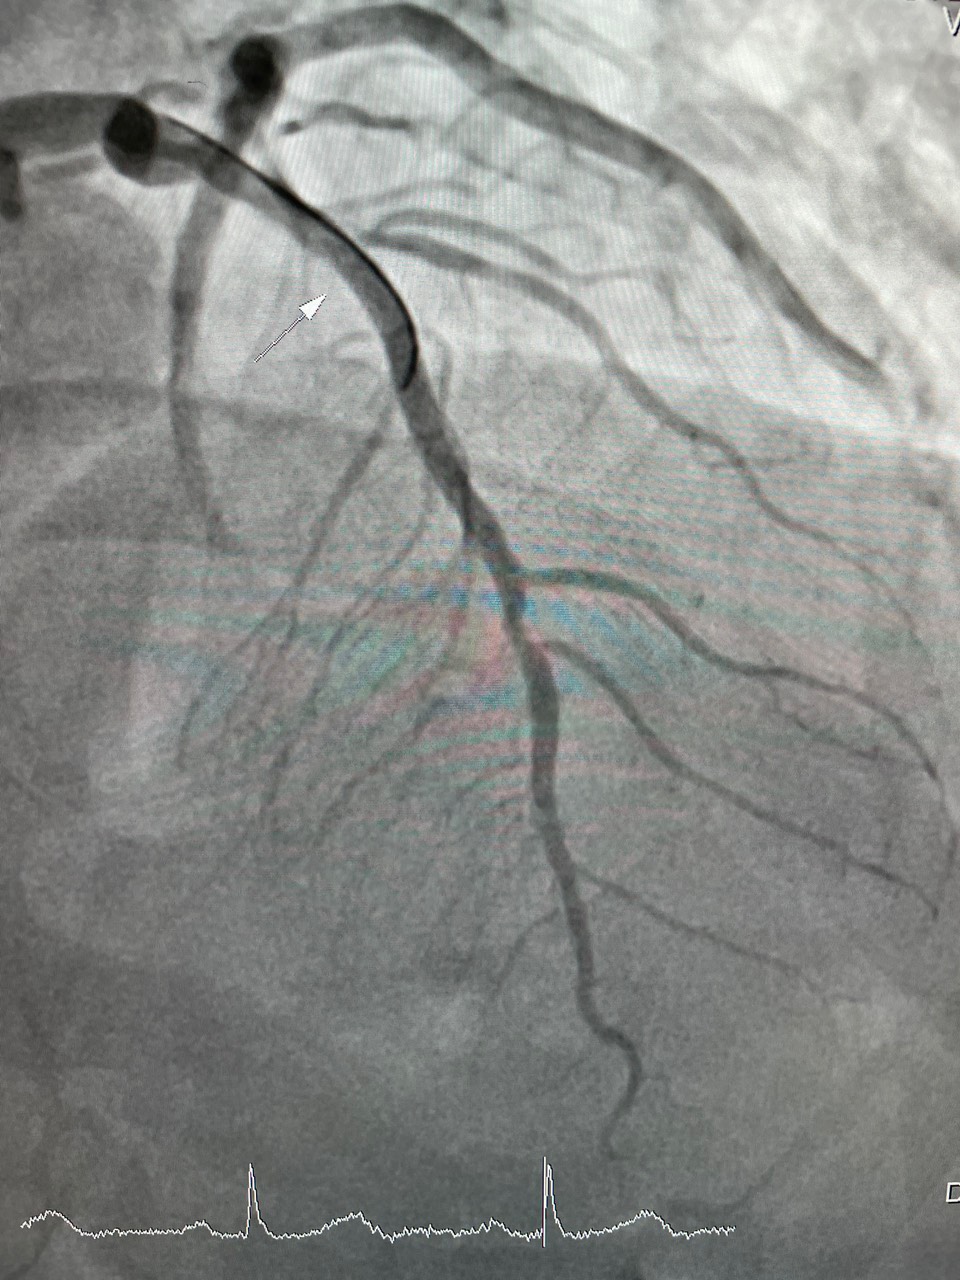

Ngày 17 tháng 5 năm 2022, Bệnh viện đa khoa tỉnh Hòa Bình tiếp nhận bệnh nhân nam, 62 tuổi, nhập khoa Hồi sức cấp cứu trong tình trạng đau dữ dội vùng ngực trái, đau như bóp nghẹt vùng sau xương ức, đau lan lên cằm và lan ra cánh tay trái. Ngoài ra, bệnh nhân rơi vào tình trạng tím tái toàn thân, vã mồ hôi, chân tay lạnh, mạch đập chậm khoảng 52 lần/phút, huyết áp 90/60mmHg. Qua thăm khám lâm sàng và một số xét nghiệm cận lâm sàng, bệnh nhân được chẩn đoán Nhồi máu cơ tim cấp (tắc mạch máu cung cấp máu cho tim). Bệnh nhân được chuyển ngay đến khoa Nội Tim mạch để chụp mạch vành cấp cứu, kết quả: huyết khối gây hẹp 95% đoạn I-II động mạch liên thất trước, hẹp 90% đoạn I động mạch vành bên phải. Kíp can thiệp động mạch vành đã tiến hành nong và đặt Stent đoạn I động mạch liên thất trước và đoạn I động mạch vành bên phải. Sau can thiệp động mạch vành của bệnh nhân được tái thông hoàn toàn, bệnh nhân hết đau ngực, huyết động ổn định. Sau 6 ngày điều trị sức khoẻ người bệnh ổn định hết đau thắt ngực.

(Hình 1: huyết khối gây hẹp 95% động mạch liên thất trước. Hình 2: sau nong và đặt Stent động mạch liên thất trước tái thông hoàn toàn)